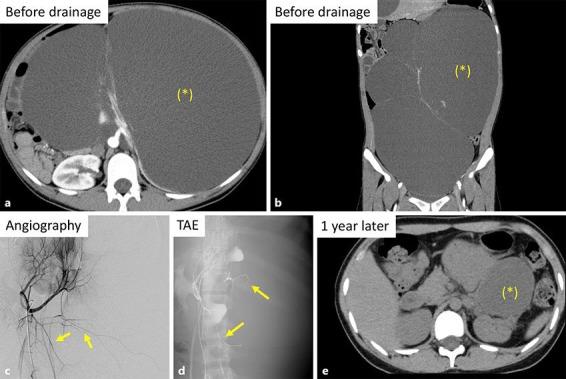

We encountered 2 patients with symptomatic huge simple renal cysts. In case 1, 4,000 mL of cyst fluid was drained via a catheter, but intracystic bleeding occurred immediately afterwards. Transcatheter arterial embolization (TAE) was performed, after which the bleeding stopped, and cyst drainage was repeated successfully. After 2 years, the total cyst volume was reduced from 11,775 mL to 75.4 mL. In case 2, TAE was performed prophylactically before drainage. Subsequently, 9,400 mL of fluid was removed from multiple cysts. After 1 year, the total cyst volume was reduced from 9,215 mL to 633 mL without bleeding. Based on these 2 cases, prophylactic TAE before drainage may be useful in patients with huge renal cysts.

我们遇到了2例有症状的巨大单纯性肾囊肿患者。病例1中,通过导管抽出了4000 mL囊液,但随后立即发生了囊内出血。进行了经导管动脉栓塞术(TAE),之后出血停止,并且成功地再次进行了囊肿引流。2年后,囊肿总体积从11775 mL减少至75.4 mL。病例2中,在引流前预防性地进行了TAE。随后,从多个囊肿中抽出了9400 mL液体。1年后,囊肿总体积从9215 mL减少至633 mL,且未发生出血。基于这2个病例,引流前预防性TAE可能对巨大肾囊肿患者有用。